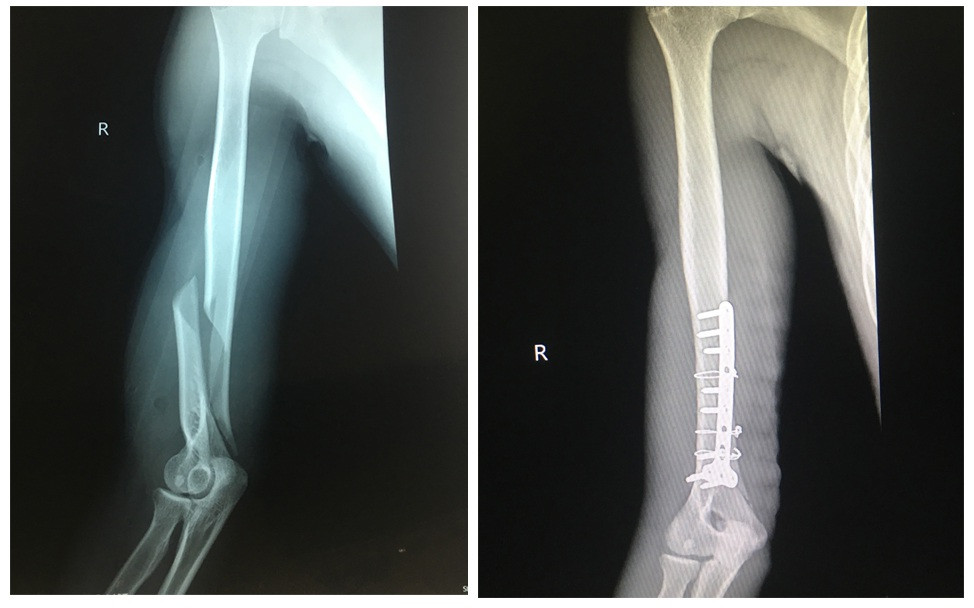

Hình ảnh phim chụp X-quang của người bệnh trước phẫu thuật (bên trái) và sau phẫu thuật (bên phải).

Câu được đưa đến Bệnh viện Việt Nam-Thụy Điển Uông Bí (Quảng Ninh) cấp cứu. Hình ảnh trên phim chụp X-quang cho thấy bệnh nhân bị gãy kín 1/3 dưới xương cánh tay phải. Bác sĩ chỉ định phẫu thuật nắn chỉnh xương và kết hợp xương nẹp vít.

Theo bác sĩ khoa Chấn thương - Chỉnh hình & Bỏng, Bệnh viện Việt Nam-Thụy Điển Uông Bí, bộc lộ ổ gãy 1/3 dưới xương cánh tay phải khi phẫu thuật các bác sĩ nhận thấy xương cánh tay bị gãy vặn xoắn đoạn chừng 8cm, di lệch nhiều, ổ gãy nhiều máu tụ. Ê kíp phẫu thuật đã tiến hành làm sạch ổ gãy, đặt lại xương và cố định lại xương cánh tay bằng nẹp, vít.